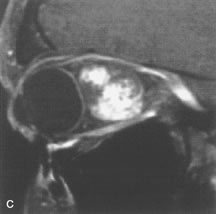

On MRI, uveal melanomas have a typical appearance that helps to differentiate them from other primary and secondary intraocular tumors as well as choroidal detachments. Pigmented melanomas are hyperintense on Tl-weighted images, hypointense on T2-weighted studies, and hyperintense on proton density–weighted examinations (Fig. 24).30,31,50,80–82 These signal characteristics have been attributed to the paramagnetic properties of melanin because of stable free radicals that shorten the T1 and T2 relaxation times. Moderate enhancement is seen on postgadolinium T2-weighted images. Gadolinium-enhanced T1-weighted images are particularly sensitive in detecting choroidal melanomas.83 MRI may be less sensitive in detecting extrascleral extension of tumor than echography performed by an experienced ultrasonographer.84

Fig. 24. A. T1- and (B) T2-weighted MR scans demonstrate a small nodular intraocular mass (arrows) that is very hyperintense on the T1-weighted scan and hypointense on the T2-weighted image. This signal intensity pattern is due to the presence of free radicals within melanin granules. C and D. Postcontrast fat-suppressed T1-weighted scans demonstrate homogeneous intense enhancement of the lesion and no evidence of seleral penetration or optic nerve invasion.